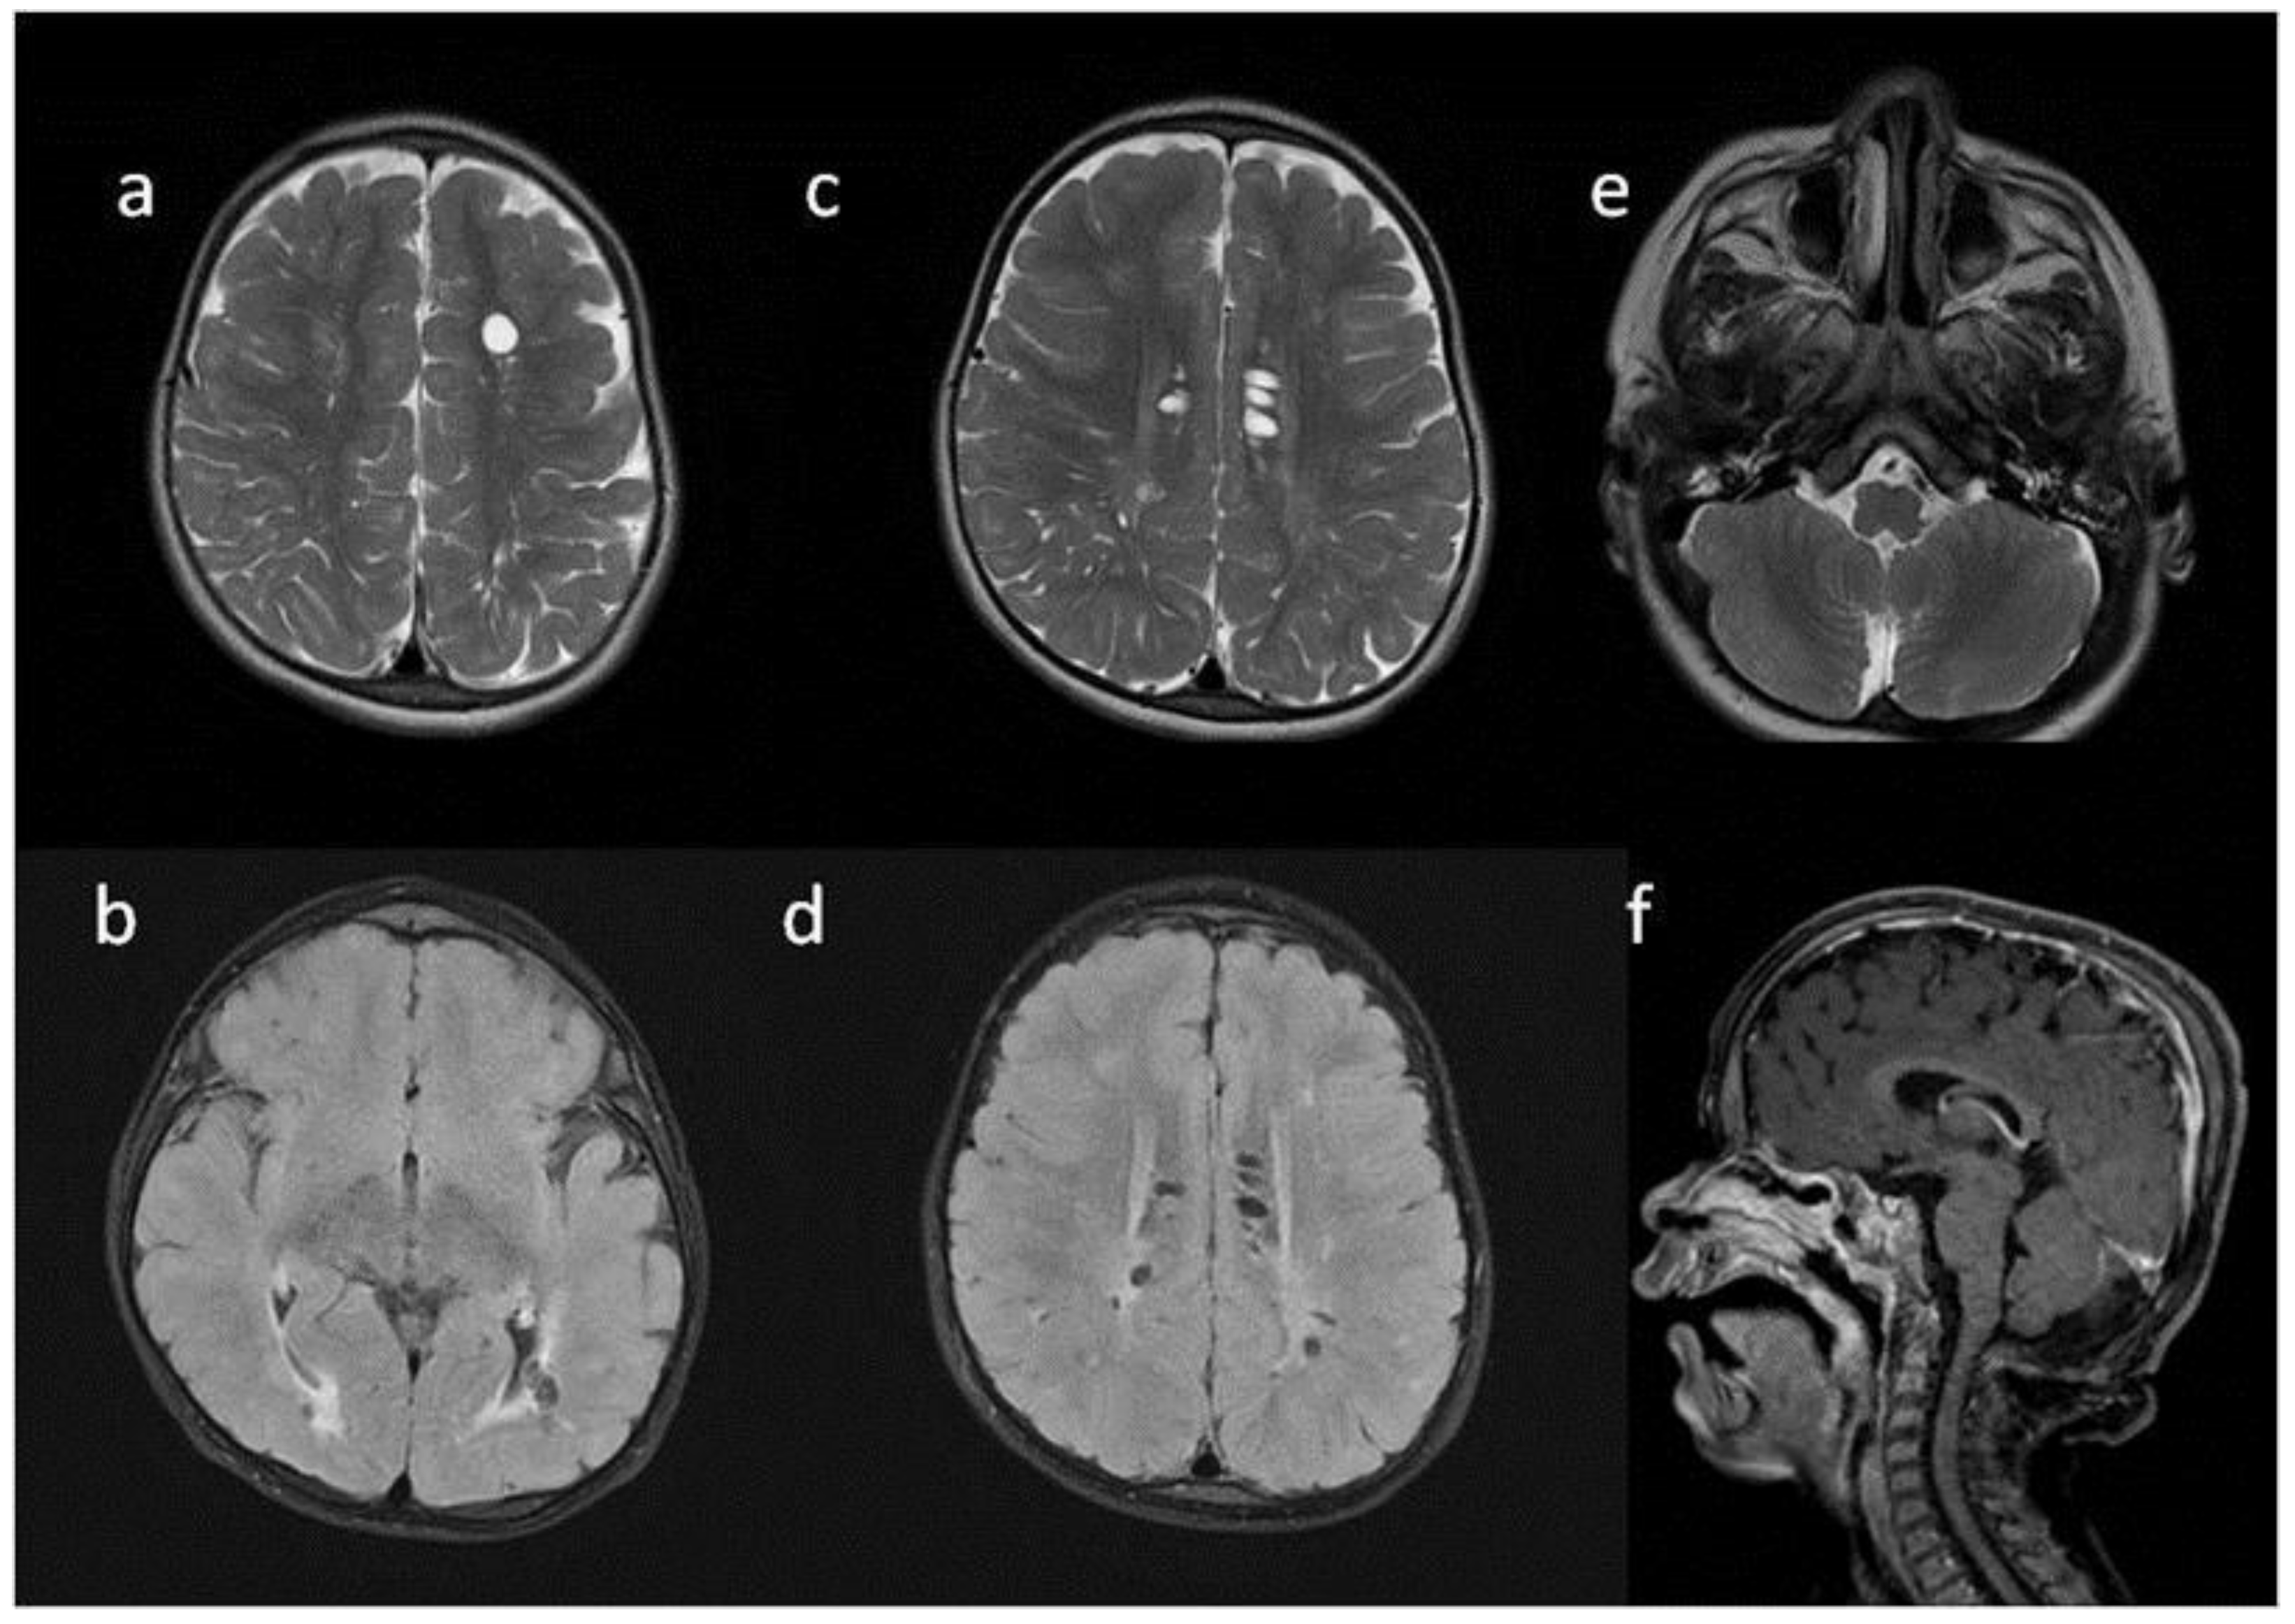

| Patient No | 1 | 2 | 3 | 4 | 5 | |

|---|---|---|---|---|---|---|

| age at exam | 4 mo | 3 yo | 1 y 2 mo | 1 y 11 mo | 3 y 2 mo | 14 yo |

| radiological imaging | ||||||

| WM signal abnormalities | + | + | + | |||

| areas of delayed myelination | + | + | + | + | + | |

| enlarged perivascular spaces | + | + | + | + | ||

| narrow corpus callosum | + | +/− | + | + | ||

| prominent ventricular system | +/− | + | +/− | + | + | |

| arachnoid cyst | + | + | ||||

| optic nerve sheath enlargement | + | + | ||||

| J-shaped sella turcica | + | + | + | +/− | + | +/− |

| craniocervical junction distortion | + | +/− | + | + | ||

| posterior fossa horns | + | + | + | + | ||

| fluid effusion temporal bone | + | + | + | + | +/− | |

| closed sagittal suture | + | + | + | |||

| vertebral bodies deformity | + | + | ||||

| intervertebral disc anomalies | + | + | ||||